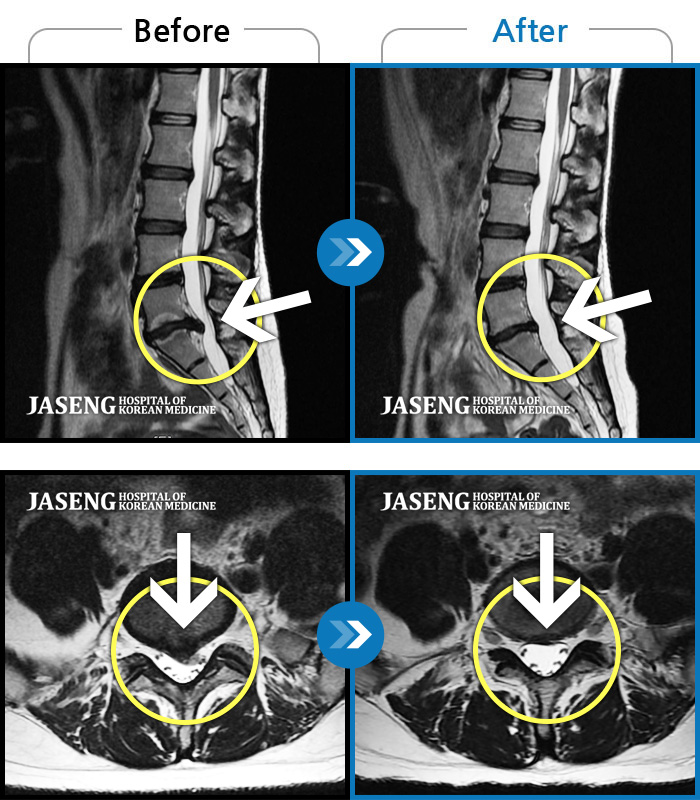

Before

After

앉아 있다가 일어설 때 통증이 증가합니다. 좌측 엉덩이부터 발까지 저립니다.

2023.08.05 ~ 2024.02.28